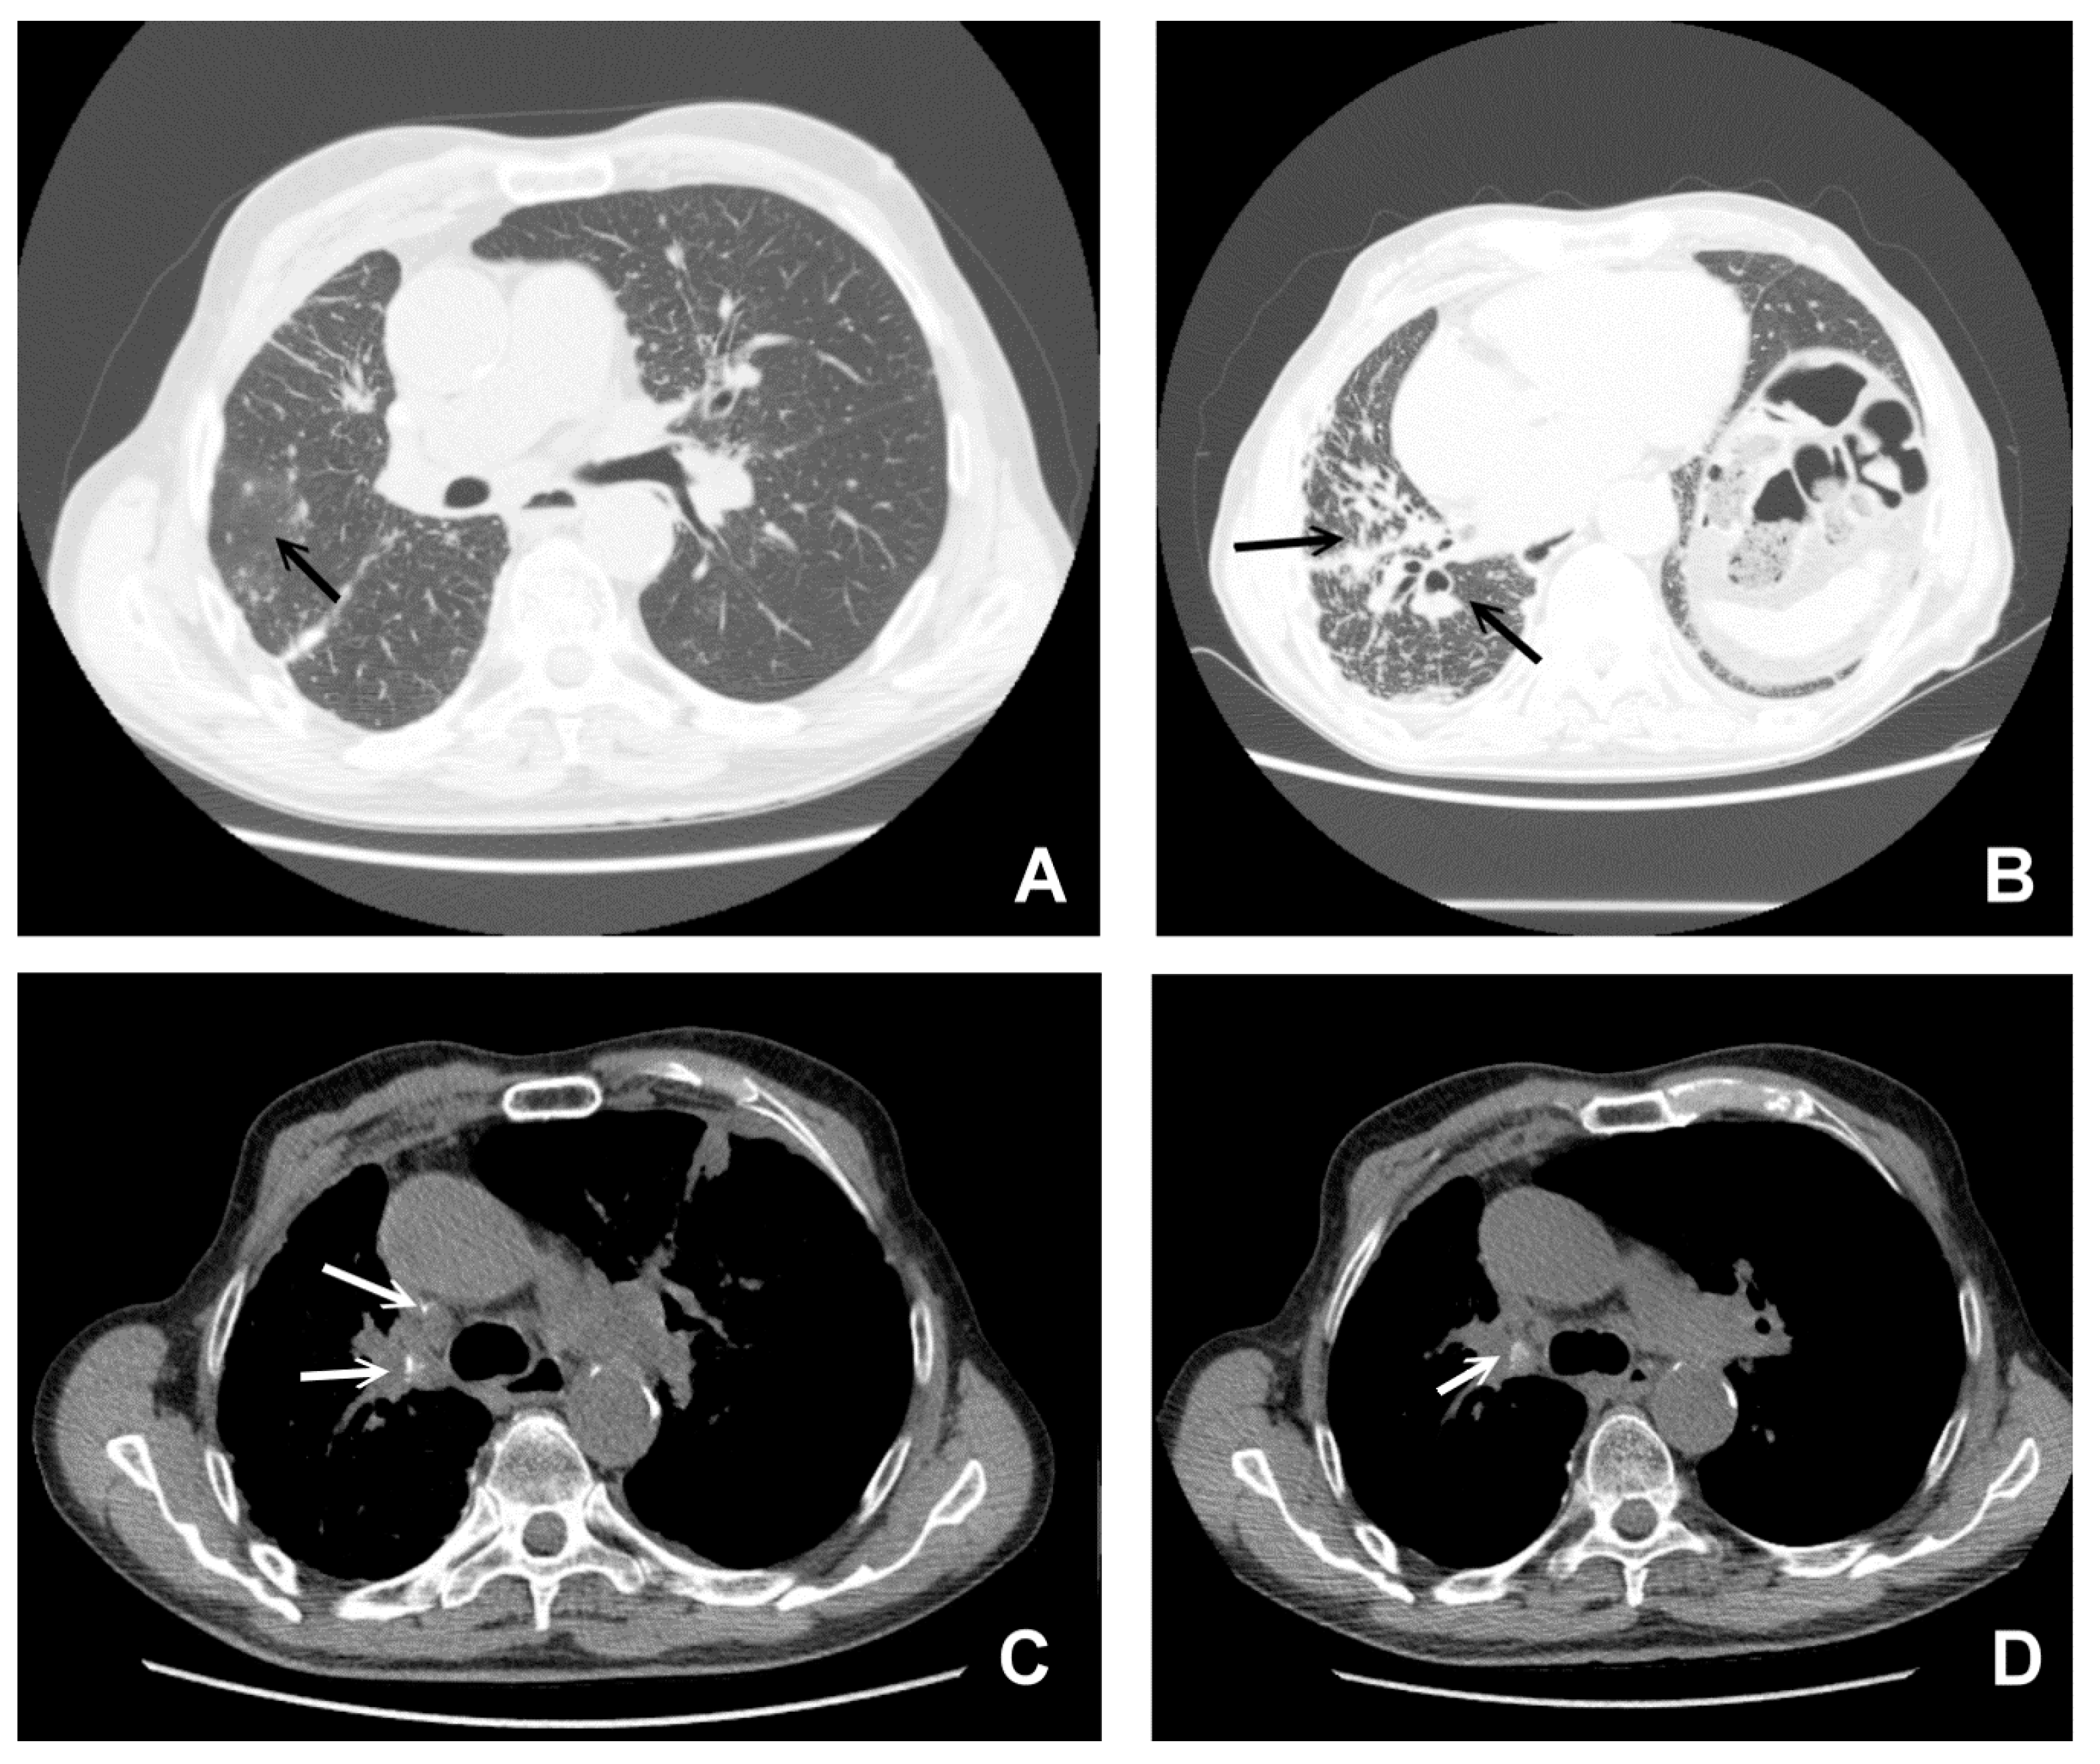

3. CT in Pulmonary Sarcoidosis, Imaging Findings and Classification

4.1. The Involvement of Liver, Spleen and Abdominal Lymph Nodes